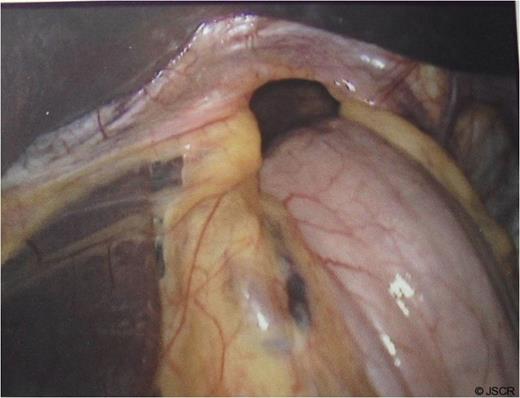

Chest pain persisted and the patient required higher pressure CPAP to maintain adequate oxygenation. Auscultation consistently showed decreased air-entry in the lung bases. On day 3, a repeat chest x-ray showed a left lower lobe collapse above the gastric bubble in the mid zone of the chest (Fig. 4 & 5). CTPA done on the same day to exclude pulmonary embolism confirmed a para-oesophageal hernia that was pushing against the left lung base. Ultrasound scan of the left chest also showed movement of the diaphragm below the gastric bubble.

Chest x-ray on 3rd post-op day showing prominent left sided collapse/ consolidation

Post-op CT-scan demonstrating the left sided pleural effusion with collapse /consolidation & patchy opacification on the right side.